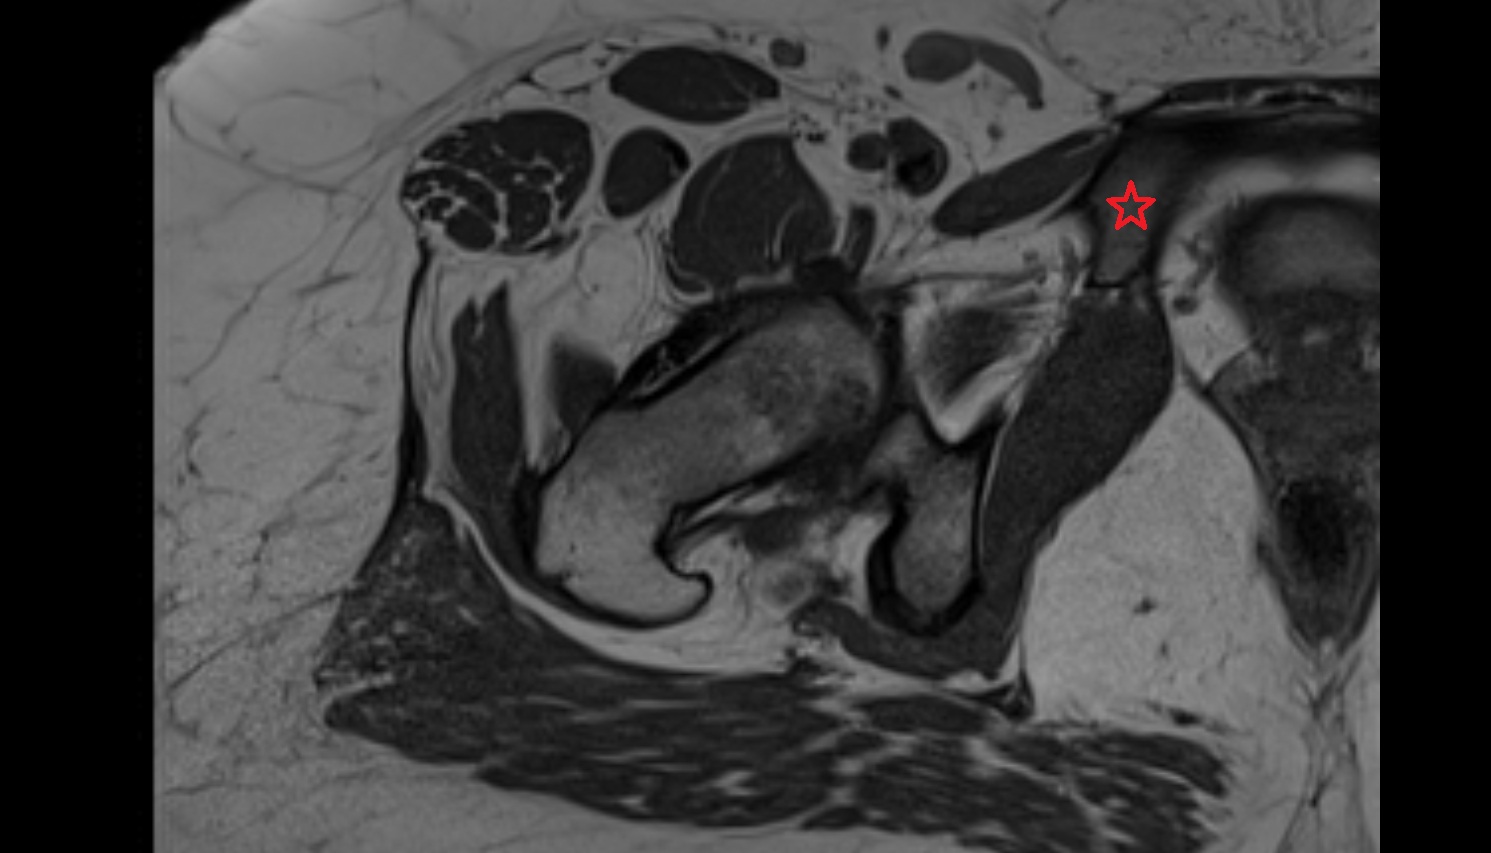

- Hip joint